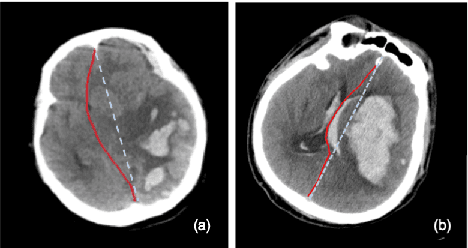

Abstract:The midline related pathological image features are crucial for evaluating the severity of brain compression caused by stroke or traumatic brain injury (TBI). The automated midline delineation not only improves the assessment and clinical decision making for patients with stroke symptoms or head trauma but also reduces the time of diagnosis. Nevertheless, most of the previous methods model the midline by localizing the anatomical points, which are hard to detect or even missing in severe cases. In this paper, we formulate the brain midline delineation as a segmentation task and propose a three-stage framework. The proposed framework firstly aligns an input CT image into the standard space. Then, the aligned image is processed by a midline detection network (MD-Net) integrated with the CoordConv Layer and Cascade AtrousCconv Module to obtain the probability map. Finally, we formulate the optimal midline selection as a pathfinding problem to solve the problem of the discontinuity of midline delineation. Experimental results show that our proposed framework can achieve superior performance on one in-house dataset and one public dataset.